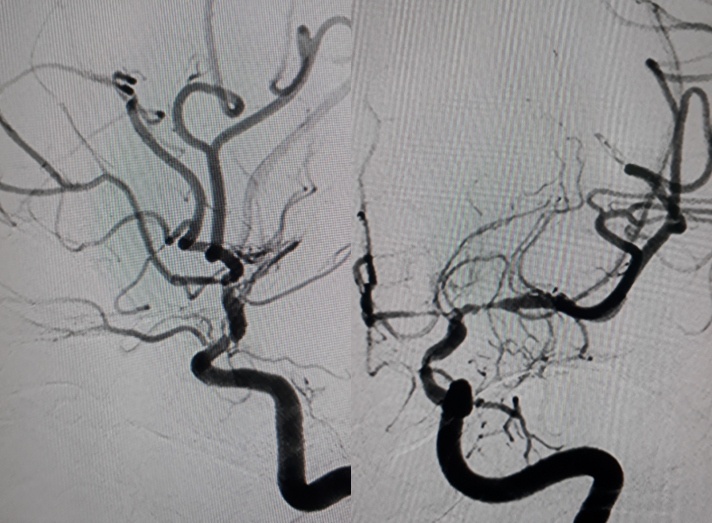

Hình chụp DSA động mạch cảnh trong phải và trái: hẹp khít động mạch não giữa hai bên đoạn M1.

Hình chụp DSA động mạch cảnh trong trái: hẹp khít động mạch cảnh trong trái đoạn mấu giường.

Hình chụp DSA động mạch đốt sống: bàng hệ cho hệ tuần hoàn trước từ hệ thống tuần hoàn sau

2. CHẨN ĐOÁN: hình ảnh điển hình của bệnh Moya Moya

Bệnh Moya Moya là bệnh lý mạch máu hẹp tại gốc một số động mạch lớn trong sọ thuộc tuần hoàn trước (thuộc động mạch cảnh trong). Quá trình hẹp dần dần nên cơ thể thích nghi bằng các tuần hoàn bàng hệ bù cho vùng thiếu hụt tuần hoàn. Tuần hoàn bàng hệ phát triển tại chỗ hẹp bằng rất nhiều mạch máu nhỏ và yếu, dễ hình thành các phình mạch nhỏ và vỡ gây chảy máu não. Nếu tuần hoàn bàng hệ một lúc nào đó không đủ cấp máu cho não sẽ gây nên nhồi máu não tái đi tái lại. Trên chụp mạch, các mạch nhỏ tại chỗ hẹp tạo nên hình “những làn khói tỏa” (puff of smoke). Bệnh lấy tên một bác sĩ người Nhật là người đầu tiên mô tả về bệnh này trong y văn.